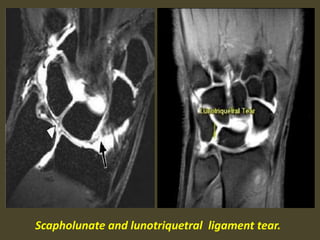

Scapholunate and lunotriquetral ligament tear.

1. Scapholunate ligament tear, dorsal angulation of the lunate and

proximal migration of the capitate consistent with a DISI deformity.

2. Tear of the lunotriquetral and triscaphe ligaments.